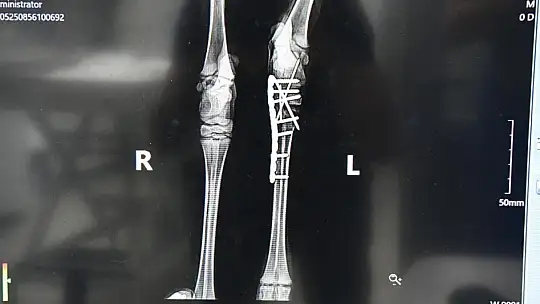

Balıkesir Büyükşehir Belediyesi Çevre Koruma ve Kontrol Dairesi Başkanlığı’na bağlı Ovaköy Sokak Hayvanları Bakımevi’nde görevli veteriner hekimler, evcil hayvanların yanı sıra doğal ortamda yaralanan hayvanların tedavi ve bakımlarını da başarılı bir şekilde yürütüyor. Doğa Koruma ve Milli Parklar Balıkesir Şube Müdürlüğü tarafından yaralı olarak bulunan yavru karaca, Ovaköy Sokak Hayvanları Bakımevi’ne getirilerek tedavi altına alındı. Ayakta durmakta zorlanan karacanın sol arka ayağına röntgen çeken Veteriner Hekim Serhat Meşe, ayağının kırık olduğunu tespit etti. Veteriner Meşe, karacayı eski sağlığına kavuşturmak için zaman kaybetmeden ameliyata aldı. Ameliyatın başarılı bir şekilde tamamlanmasının ardından karaca yeniden ayağa kalktı.

Başarılı bir operasyon gerçekleştirdiklerini belirten Veteriner Hekim Serhat Meşe, “Karacanın sol arka ayağında (tarsometatarsal ) eklemde kırık tespit edilmesinin ardından kross pin + plaka uygulayarak stabilize ettik. Şu anda karacamızın neşesi yerinde. Ciddi bir ameliyat atlattı, biraz ağrıları olacak. Ayağına plaka uygulaması yaptığımız için bir ay boyunca Ovaköy Sokak Hayvanları Bakımevi’nde bizim gözetimimiz altında kalacak. Karacamız genç olduğu için hızlı bir şekilde toparlayacaktır. Merkezimizde hastalıkların tespit edilmesi ve tedavi sürecinin sorunsuz bir şekilde yapılabilmesi için tüm araç gereçlerimiz mevcut. Bu sayede merkezimize gelen hayvanlarımıza sadece iyileşmek için çaba göstermeleri gerekiyor. Merkezimizin tam donanımlı olarak hizmet verebilmesi için hiç şeyden kaçınmayan Başkanımız Yücel Yılmaz’a çok teşekkür ediyorum” dedi.